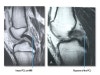

MRI는 PCL 파열, 인대, 반월상 연골, 관절 연골의 동반손상을 확인하는 데 유용합니다.

급성기에는 MRI에서 후방 십자인대 손상을 잘 관찰할 수 있으나, 후방 십자인대의 경우 손상 후에 늘어난 상태에서 치유되는 경우가 많아 만성 손상의 경우 MRI에서 연속성이 있는 후방 십자인대가 관찰되는 경우가 많으므로 주의해야합니다.

MRI : 후방 십자인대 손상(Posterior cruciate ligament injury, PCL injury)